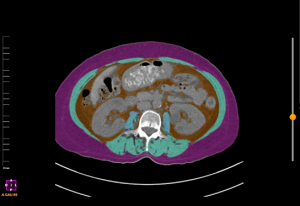

・ 第3腰椎レベルのCT画像で測定した骨格筋量を基準とし、血清クレアチニン、シスタチンC、BMIなどを用いて解析しました。

【図】第3腰椎(L3)レベルCT画像を用いた骨格筋量測定図。本図は測定方法を示す目的で掲載しており、論文中の図とは異なる。

骨格筋指数(SMI): 第3腰椎レベルでのCT画像における筋肉の断面積を身長の二乗で除した値。体格差を補正した筋肉量の客観的指標として国際的に用いられています。